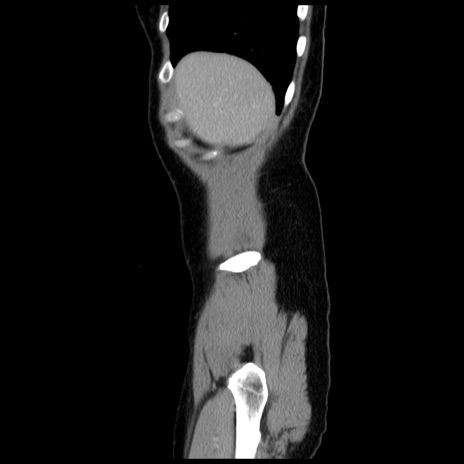

横断像

【症例】 50歳代女性

【主訴】 腹痛

【現病歴】前日生レバーを食べた。今朝に排便あり。 昼前に突然発症の腹痛を生じ、当院救急外来を受診した。

【既往歴】 子宮筋腫にてで子宮全摘後

【身体所見】 意識清明、腹部:平坦、軟、下腹部やや左を中心に圧痛・反跳痛あり、筋性防御あり

【データ】WBC 7800、CRP 0.07